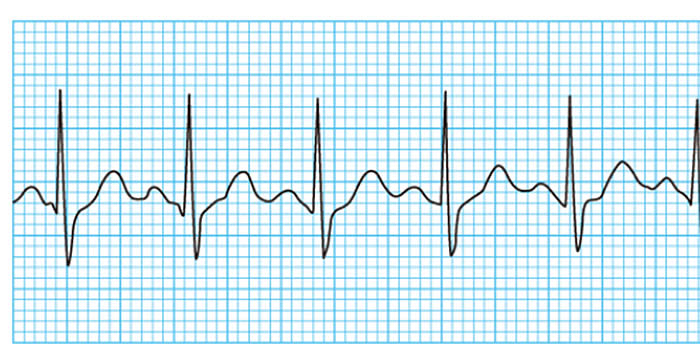

心臓は本来、一定のリズムで動いて全身に血液を送っています。

不整脈とは、このリズムが乱れて「脈が速くなったり、遅くなったり、不規則になる」状態のことです。

【こんな症状はありませんか?】

・動悸、めまい、ふらつき。重症の場合には意識を失うこともあります。

・症状がない場合もありますが、放置すると脳梗塞や心不全につながることがあります。

心電図 ABI 心エコー 頸動脈エコー

ホルター心電図(24時間)